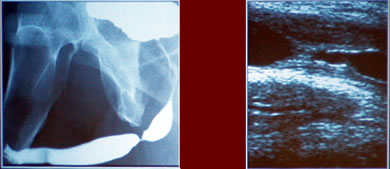

Стриктура

уретры

Простая

Короткая